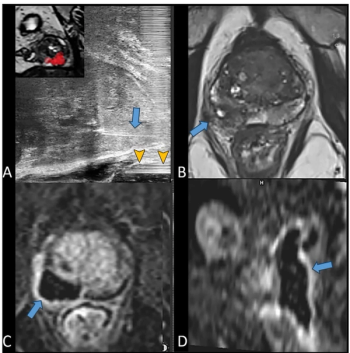

Study: MRI-Based AI Enhances Detection of Seminal Vesicle Invasion in Prostate Cancer